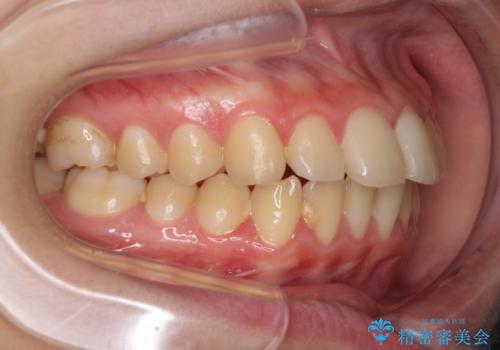

- 口元が出てるのが気になるとのことで来院されました。

歯のがたつきはあまりなかったのですが、口唇が閉じずらく、口元の突出感が確認できました。

上下左右の歯を1本ずつ抜歯して、そのスペースを利用して口元を引っ込める計画としました。